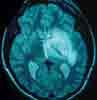

You order an emergent CT scan.

The CT scan shows a ringenhancedshadow in the frontalparietal area with cerebral edemaand encroachment on the ventricularsystem (Figure). In a patientwith advanced AIDS, these CTfindings narrow the differential tocerebral lymphoma and Toxoplasmaabscess. The negative Toxoplasmatiter makes Toxoplasma abscessless likely than cerebrallymphoma,D.

Hospital course. The patient isgiven sulfadiazine, pyrimethamine,clindamycin, dexamethasone, andintravenous phenytoin. Ventilatorysupport is required to protect hisairway. His seizures continue.A neurosurgeon is consulted;stereotactic biopsy of the ring-enhancedlesion reveals non-Hodgkinlymphoma. The hematologyoncologyservice recommends intrathecalcytarabine; intravenouschemotherapy with cyclophosphamide,doxorubicin, vincristine, andprednisone (CHOP); and cranialirradiation.